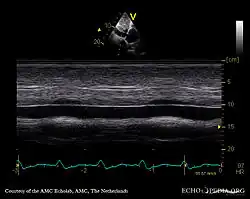

Echocardiography

If pulmonary hypertension is suspected based on the above assessments, echocardiography is performed as the next step.[13][16][59] A meta-analysis of Doppler echocardiography for predicting the results of right heart catheterization reported a sensitivity and specificity of 88% and 56%, respectively.[61] Thus, Doppler echocardiography can suggest the presence of pulmonary hypertension, but right heart catheterization (described below) remains the gold standard for diagnosis of PAH.[13][16] Echocardiography can also help to detect congenital heart disease as a cause of pulmonary hypertension.[13]